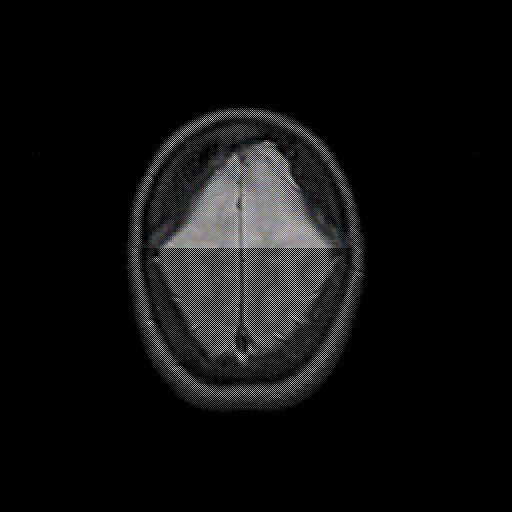

overlay : Slice 46

Slice 46

MRCBFCBF with

T1PDT2T1PDT2